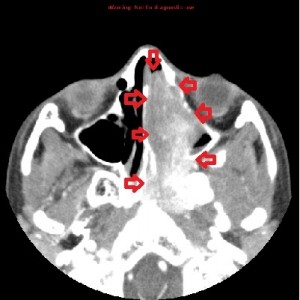

First panel, left to right: Axial contrast-enhanced maxillofacial CT scan in soft-tissue window from superior to inferior, showing a large, avidly enhancing mass in the left nasal fossa, extending posteriorly into the left nasopharnx and crossing into the right nasopharynx behind the nasal septum. Note opacification of the right and left maxillary sinuses, possibly from disturbed drainage.

Second panel, left to right: The same set of images as in the first panel, but in bone window, showing bowing of the medial wall of the left maxillary sinus and opacified maxillary sinuses. There is no bone destruction or invasion.